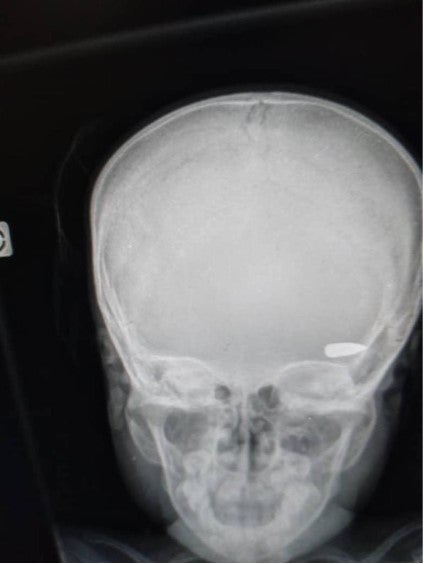

Yon imaj radyografi ki montre bal nan tèt yon timoun ki viktim pandan afwontman ant gwoup kriminèl nan katye Brooklyn nan komin Site Solèy nan kòmansman Avril 2023.